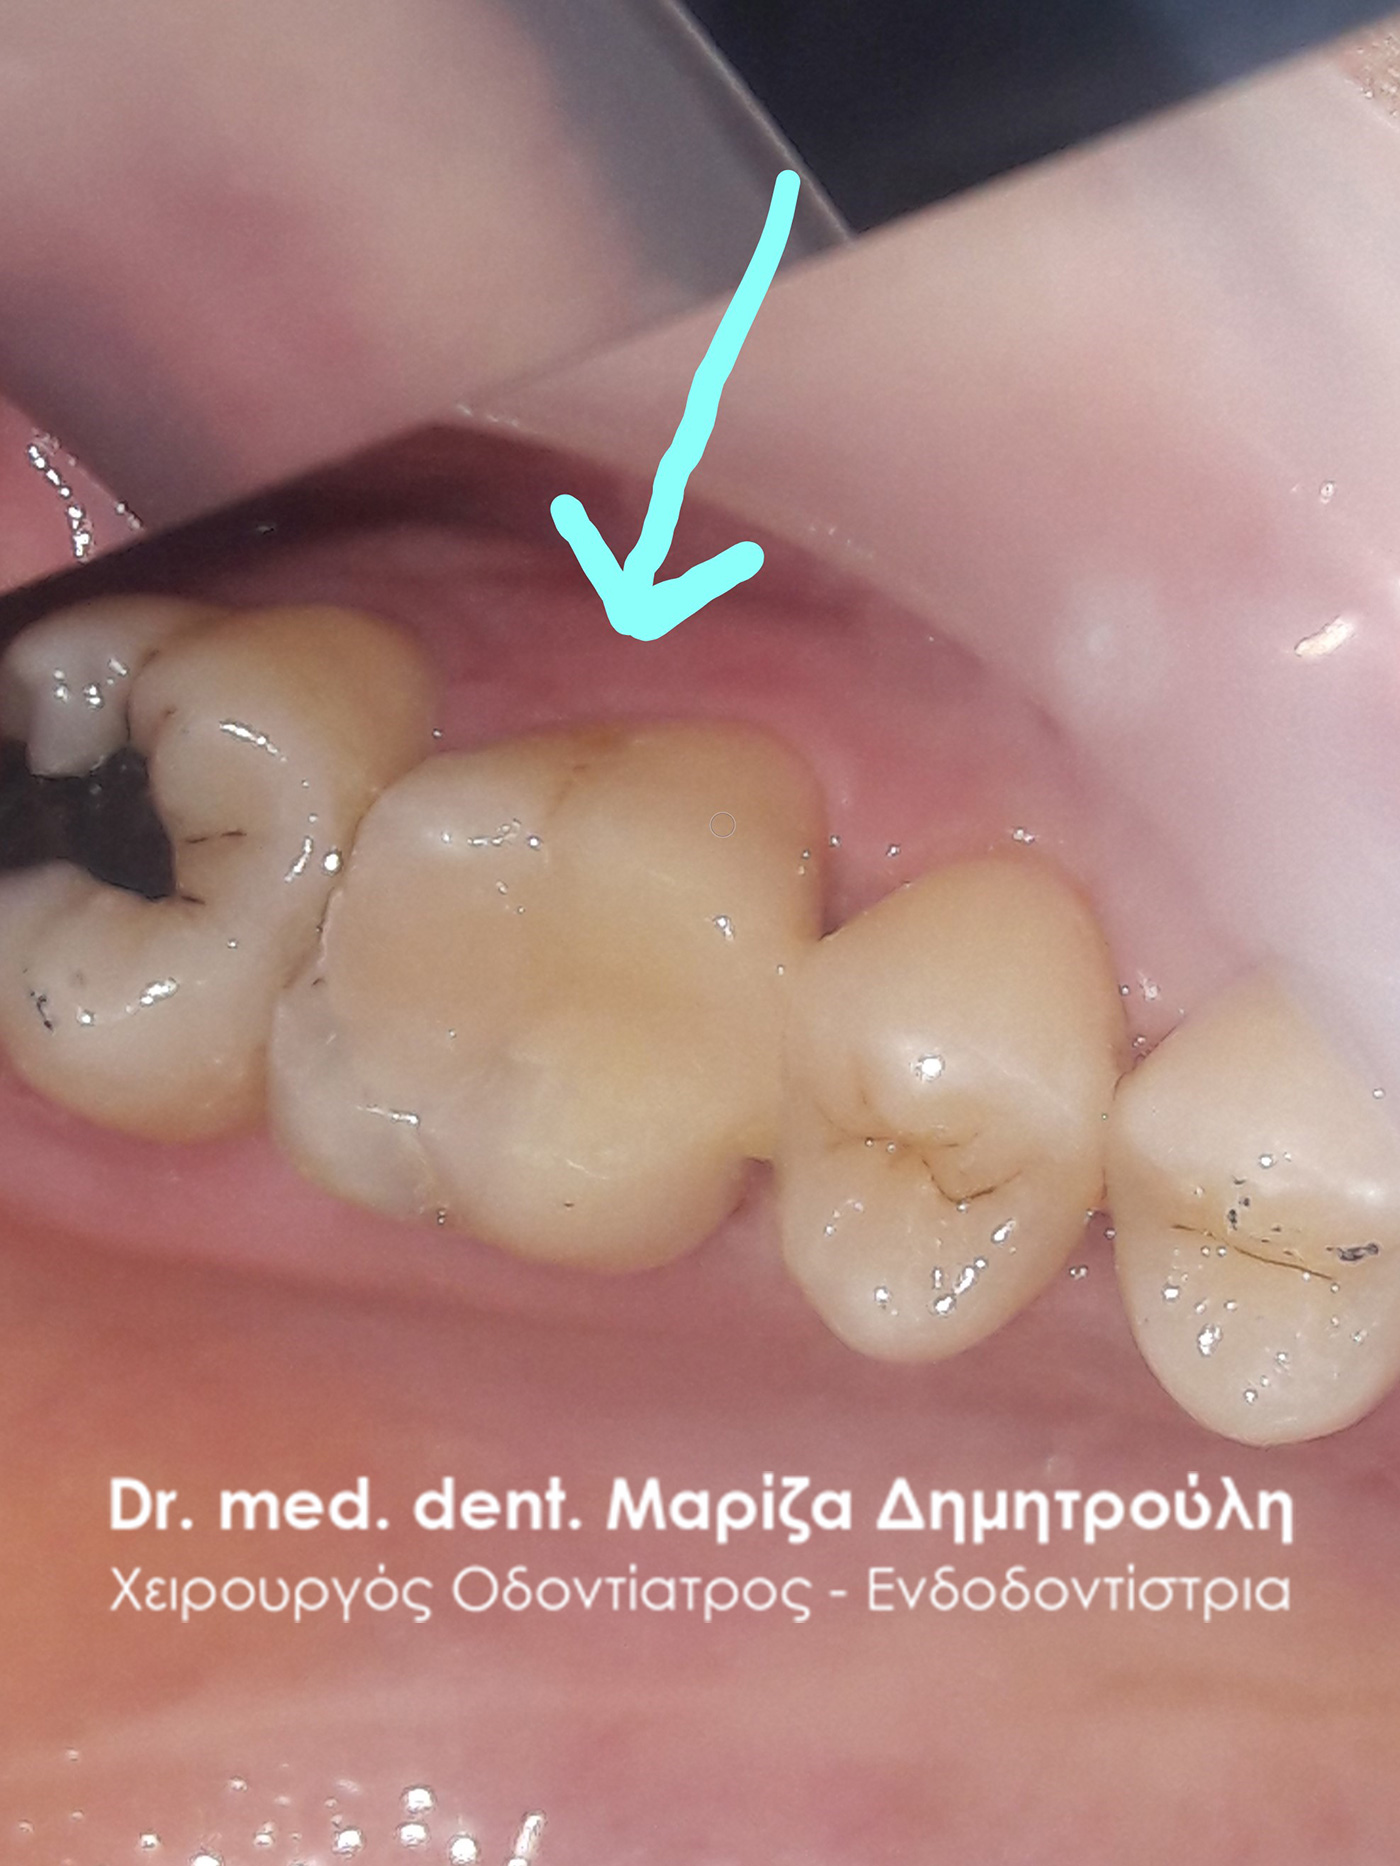

Removal of amalgam (silver) filling

BEFORE

Photo of caries after removal of old black tooth filling